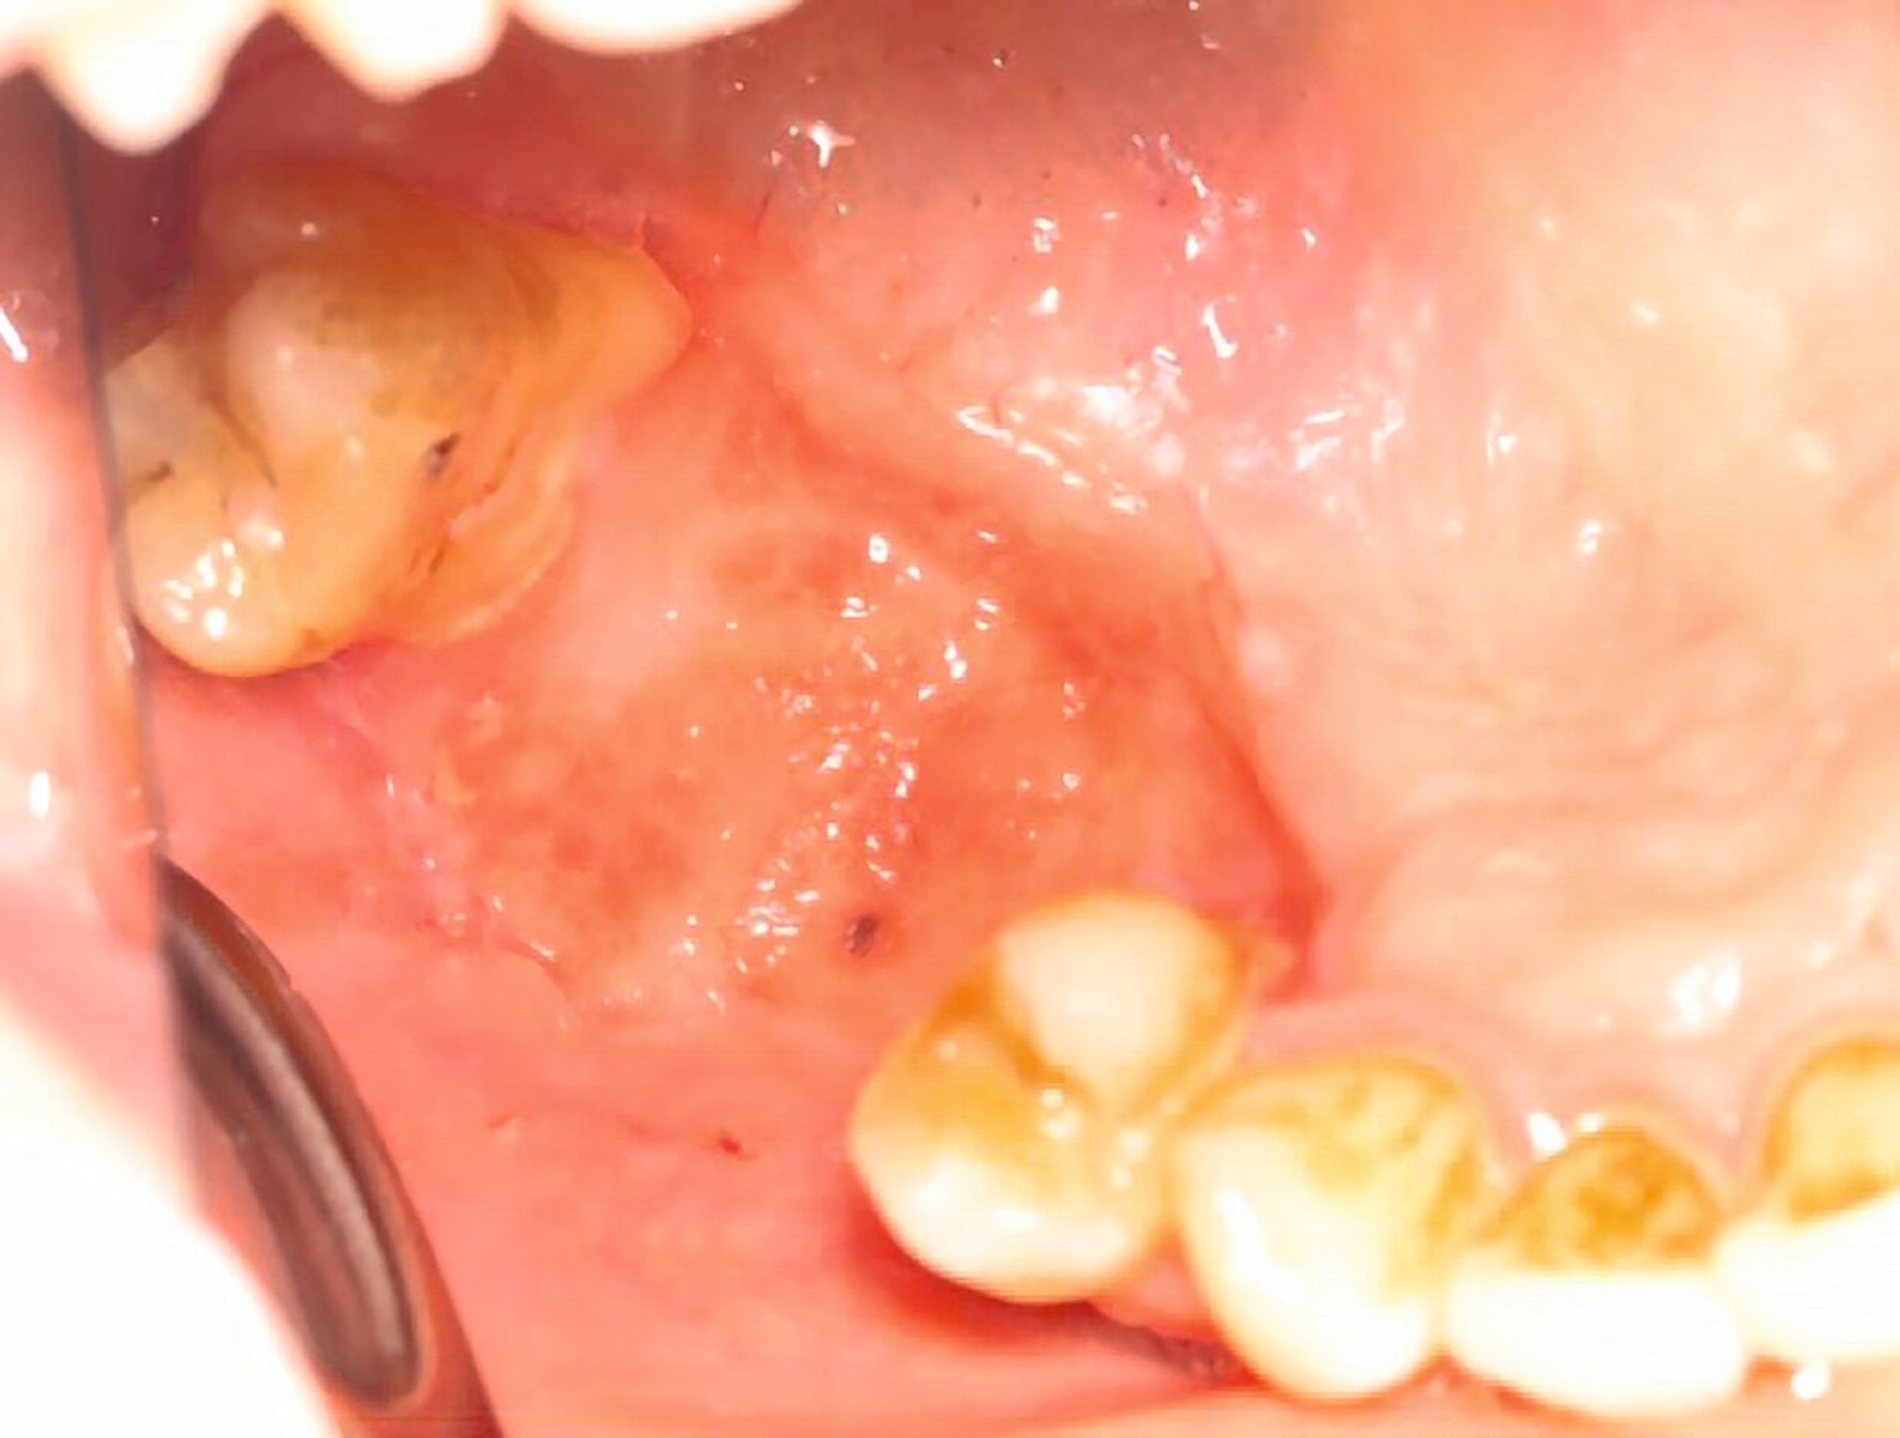

Im Verlauf der nächsten vier Wochen zeigte sich keine weitere weichgewebige Granulation (Abbildung 4). Vier Monate nach dem Spülunfall grenzte sich in der DVT-Bildgebung ein Sequester regio 15/16 ab (Abbildung 5), weshalb die Patientin nun zur operativen Sequesterotomie vorbereitet wurde. Der Sequester ließ sich zusammen mit Zahn 16 im operativen Eingriff vollständig und komplikationslos entfernen (Abbildung 6).